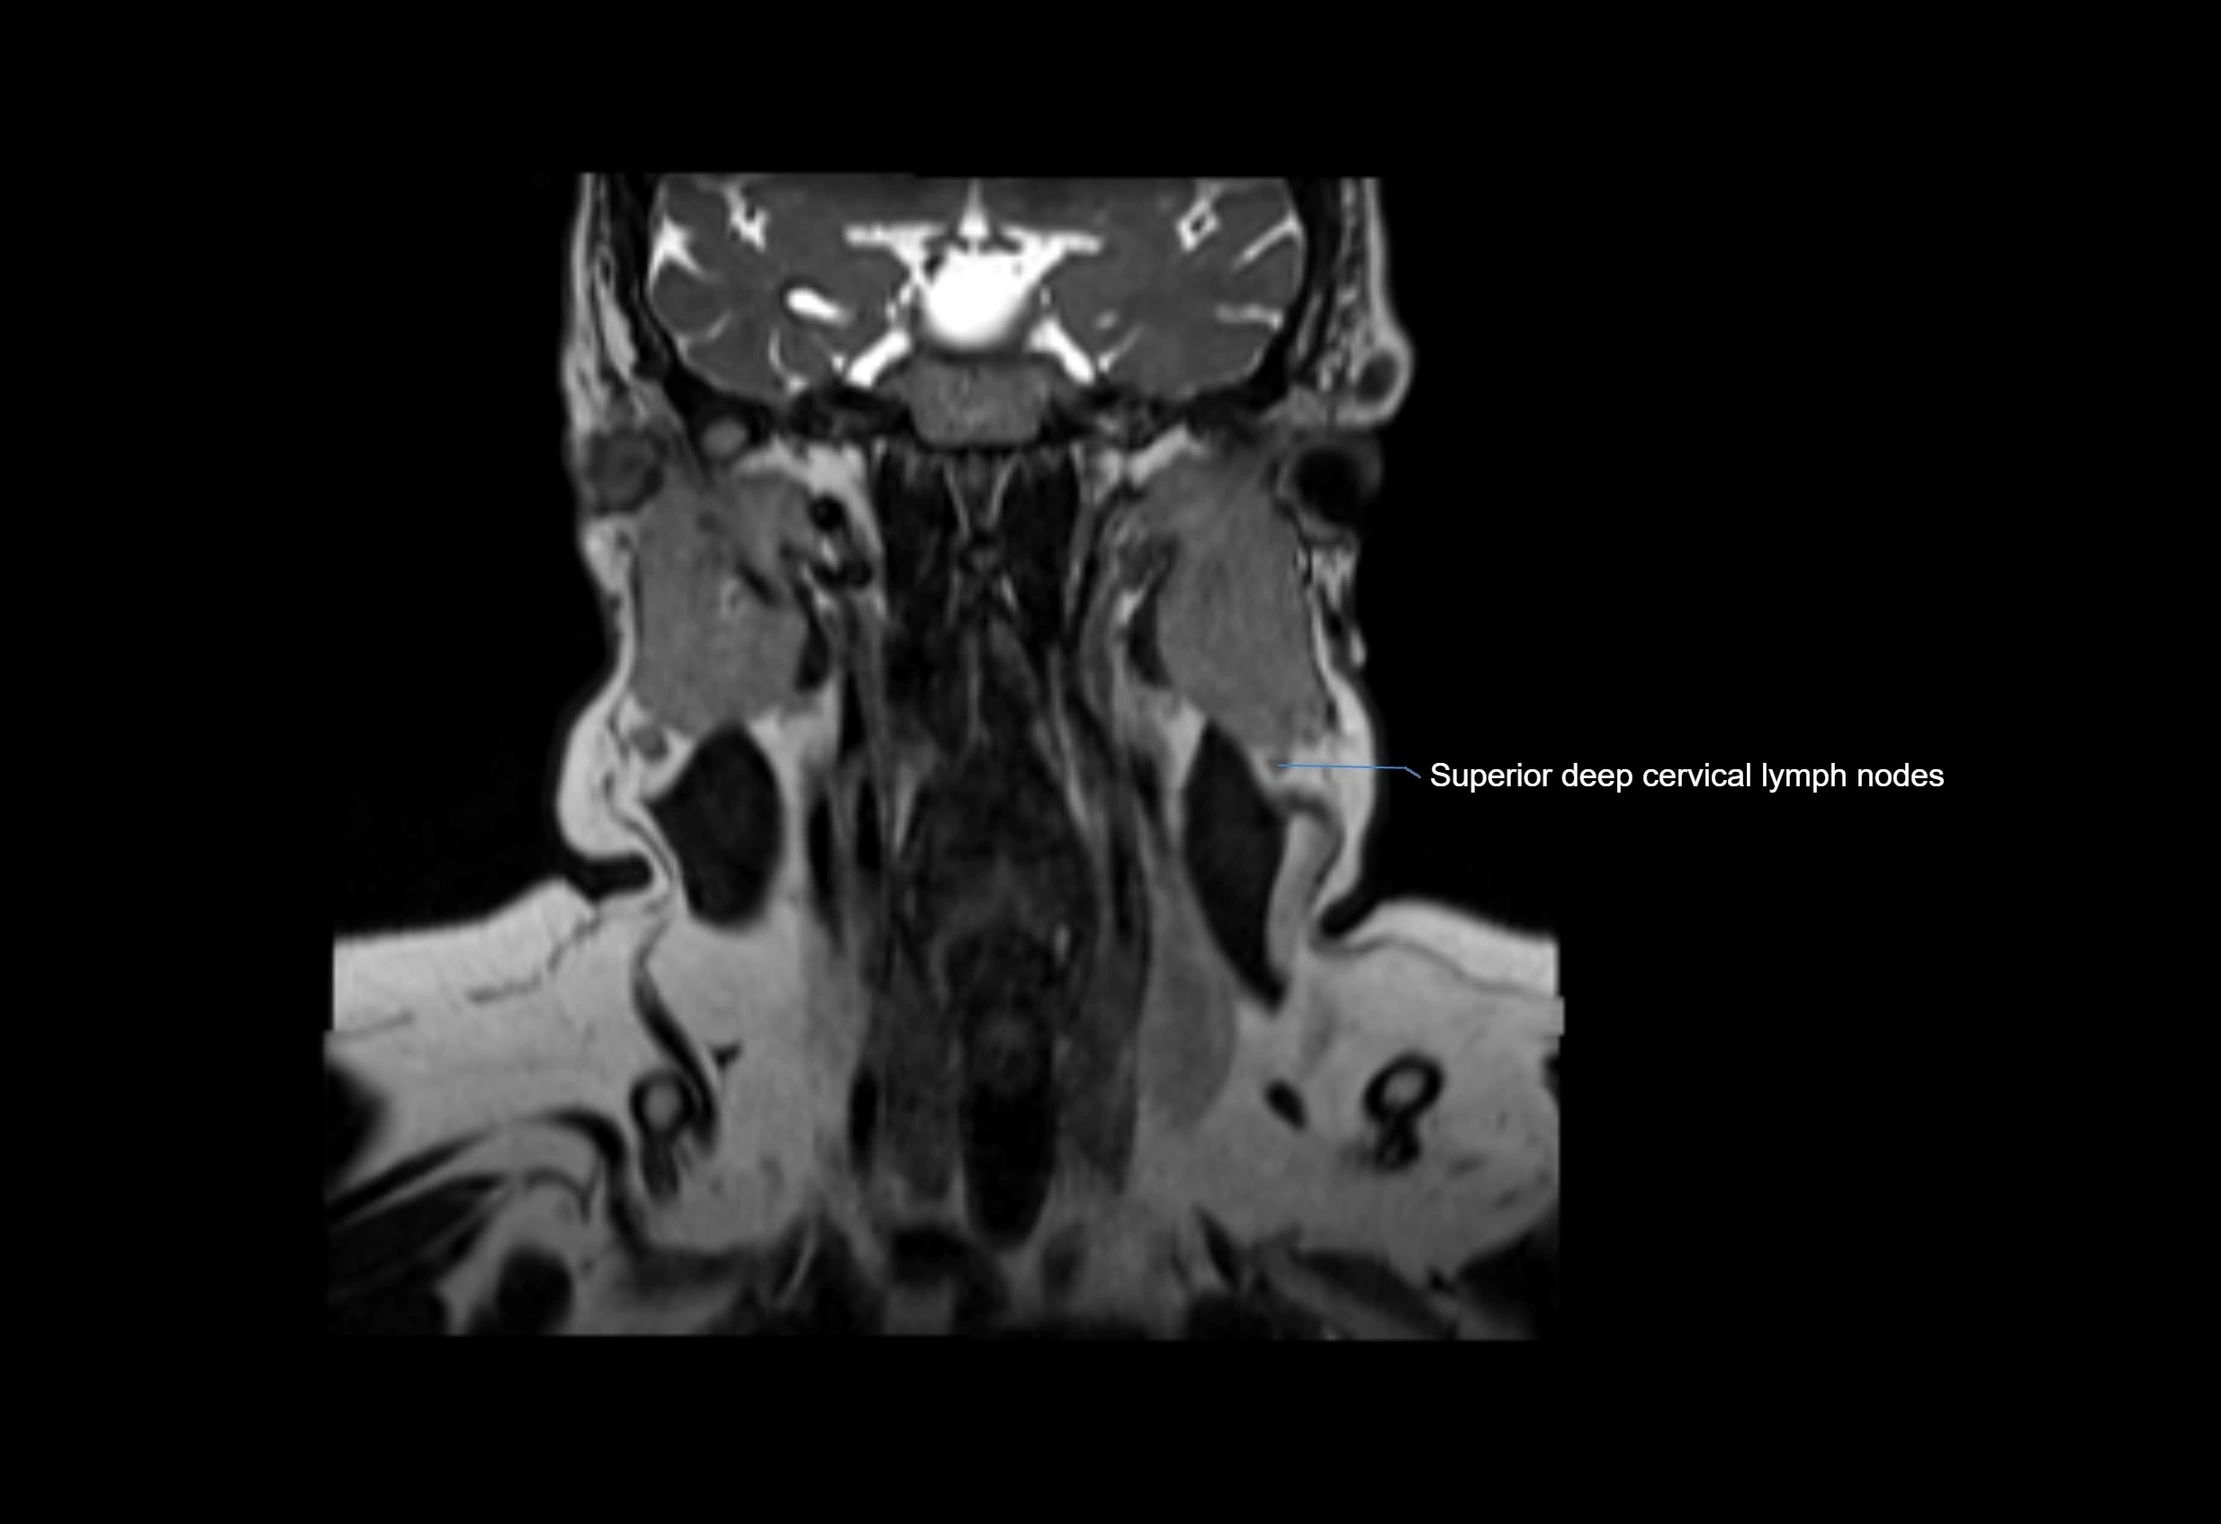

• Found along primary lymph node chains, including preauricular, submandibular, parotid, and occipital regions

• Embedded in subcutaneous fat or superficial fascia, often lateral or posterior to primary nodes

MRI Appearance

T1-weighted images:

• Normal accessory nodes appear as small, oval hypointense to intermediate signal structures within subcutaneous fat

• Surrounded by hyperintense fat, enhancing contrast for visualization

• Pathological nodes may appear enlarged or rounded, sometimes with cortical thickening

T2-weighted images:

• Nodes show intermediate signal, with surrounding fat bright

• Useful for detecting edema, inflammation, or infiltration

• Fatty hilum may appear slightly hyperintense relative to cortex

MRI images

image